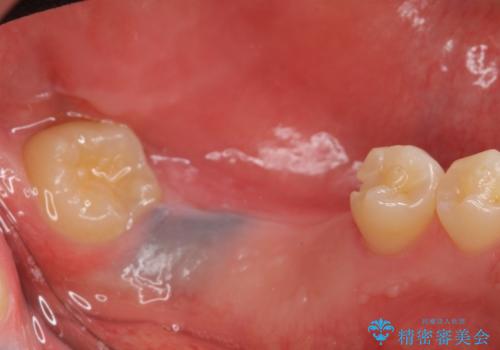

左下にインプラント(ストローマン)を2本埋入し、オールセラミッククラウンによる補綴を行いました。

オールセラミッククラウンについて

今回用いたオールセラミッククラウンはジルコニアフレームという白い素材の上にセラミックを盛っているため、審美性が非常に高いのが特徴です。

また、ジルコニアは人工ダイヤモンドの材料にも使われているほど高い強度を持っており、そのためオールセラミッククラウンは審美性だけでなく、奥歯やブリッジの補綴も可能とするクラウンです。